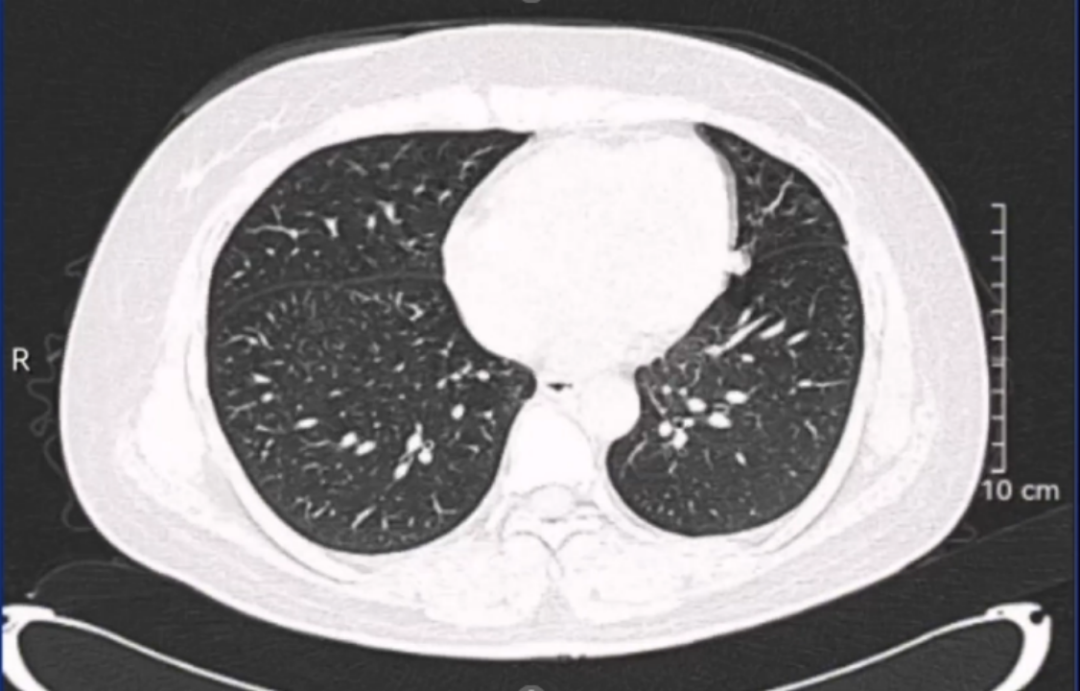

患者女性,34岁,因左肾肿瘤行左肾切除术,术后1年发现局部复发伴肺部转移。患者于2022年6月,因左肾血管平滑肌脂肪瘤在外院接受左肾切除术,2023年7月患者复查发现左侧腹膜后占位,2023-07-21外院超声造影:1.左肾切除术后;2.左侧腹膜后低回声团块,呈“不均匀性增强”(MT可能性大),2023-07-21外院肺部CT:双肺新增多发结节影,考虑转移瘤。2023-07-24在外院行超声引导下左侧腹腔肿物粗针穿刺活检术,病理回报:腹膜后淋巴结送检标本镜下见上皮样血管平滑肌脂肪瘤伴坏死,请结合临床。免疫组化结果: HMB45、MelanA阳性,Desmin少量阳性,CK-pan、CD10、Ihibin-a 阴性。目前诊断:1.左侧腹膜后上皮样血管平滑肌脂肪瘤;2.左肾切除术后。此次会诊的目的:下一步治疗方案?手术?化疗?靶向治疗?

影像科周秀秀主治医师:患者腹部CT影像显示:左侧腹膜后血管平滑肌脂肪瘤,肿瘤体积较大,直径达10cm以上,病灶中央可见坏死灶,同时肺部CT显示双肺新增多发结节影,考虑为转移瘤,提示该肿瘤进展较快,结合病理报告,考虑属于特殊类型的血管平滑肌脂肪瘤。